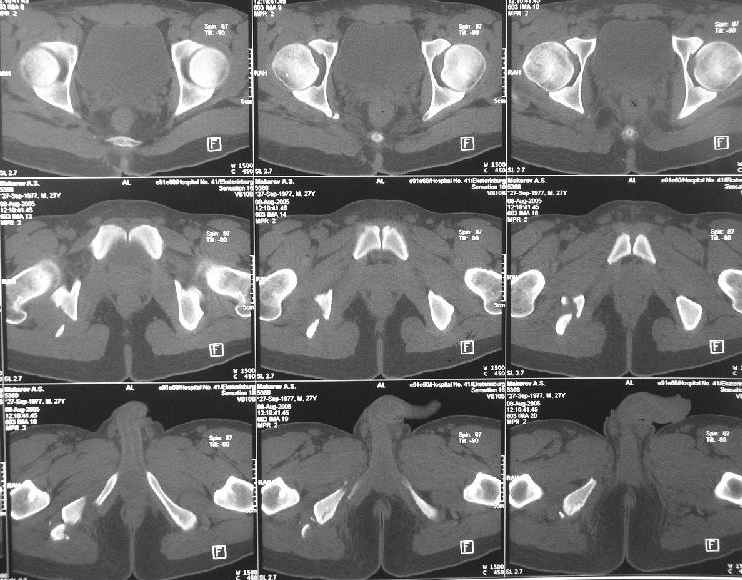

Уважаемые коллеги, хотелось бы услышать ваше мнение по тактике лечения следующего пациента: мужчина, 27 лет, получил травму на производстве 25 июня - перелом правого седалищного бугра (кт и рентгенограмма прилагаются).

Больной жалуется на боли - сидя и при ходьбе. В настоящее время ходит, хромая, без дополнительной опоры. Оторвавшийся седалищный бугор состоит из 2-х фрагментов, один из которых раздражает седалищный нерв. Если кто-то имеет опыт оперативного лечения подобных повреждений, подскажите из какого доступа лучше это сделать. Заранее спасибо.